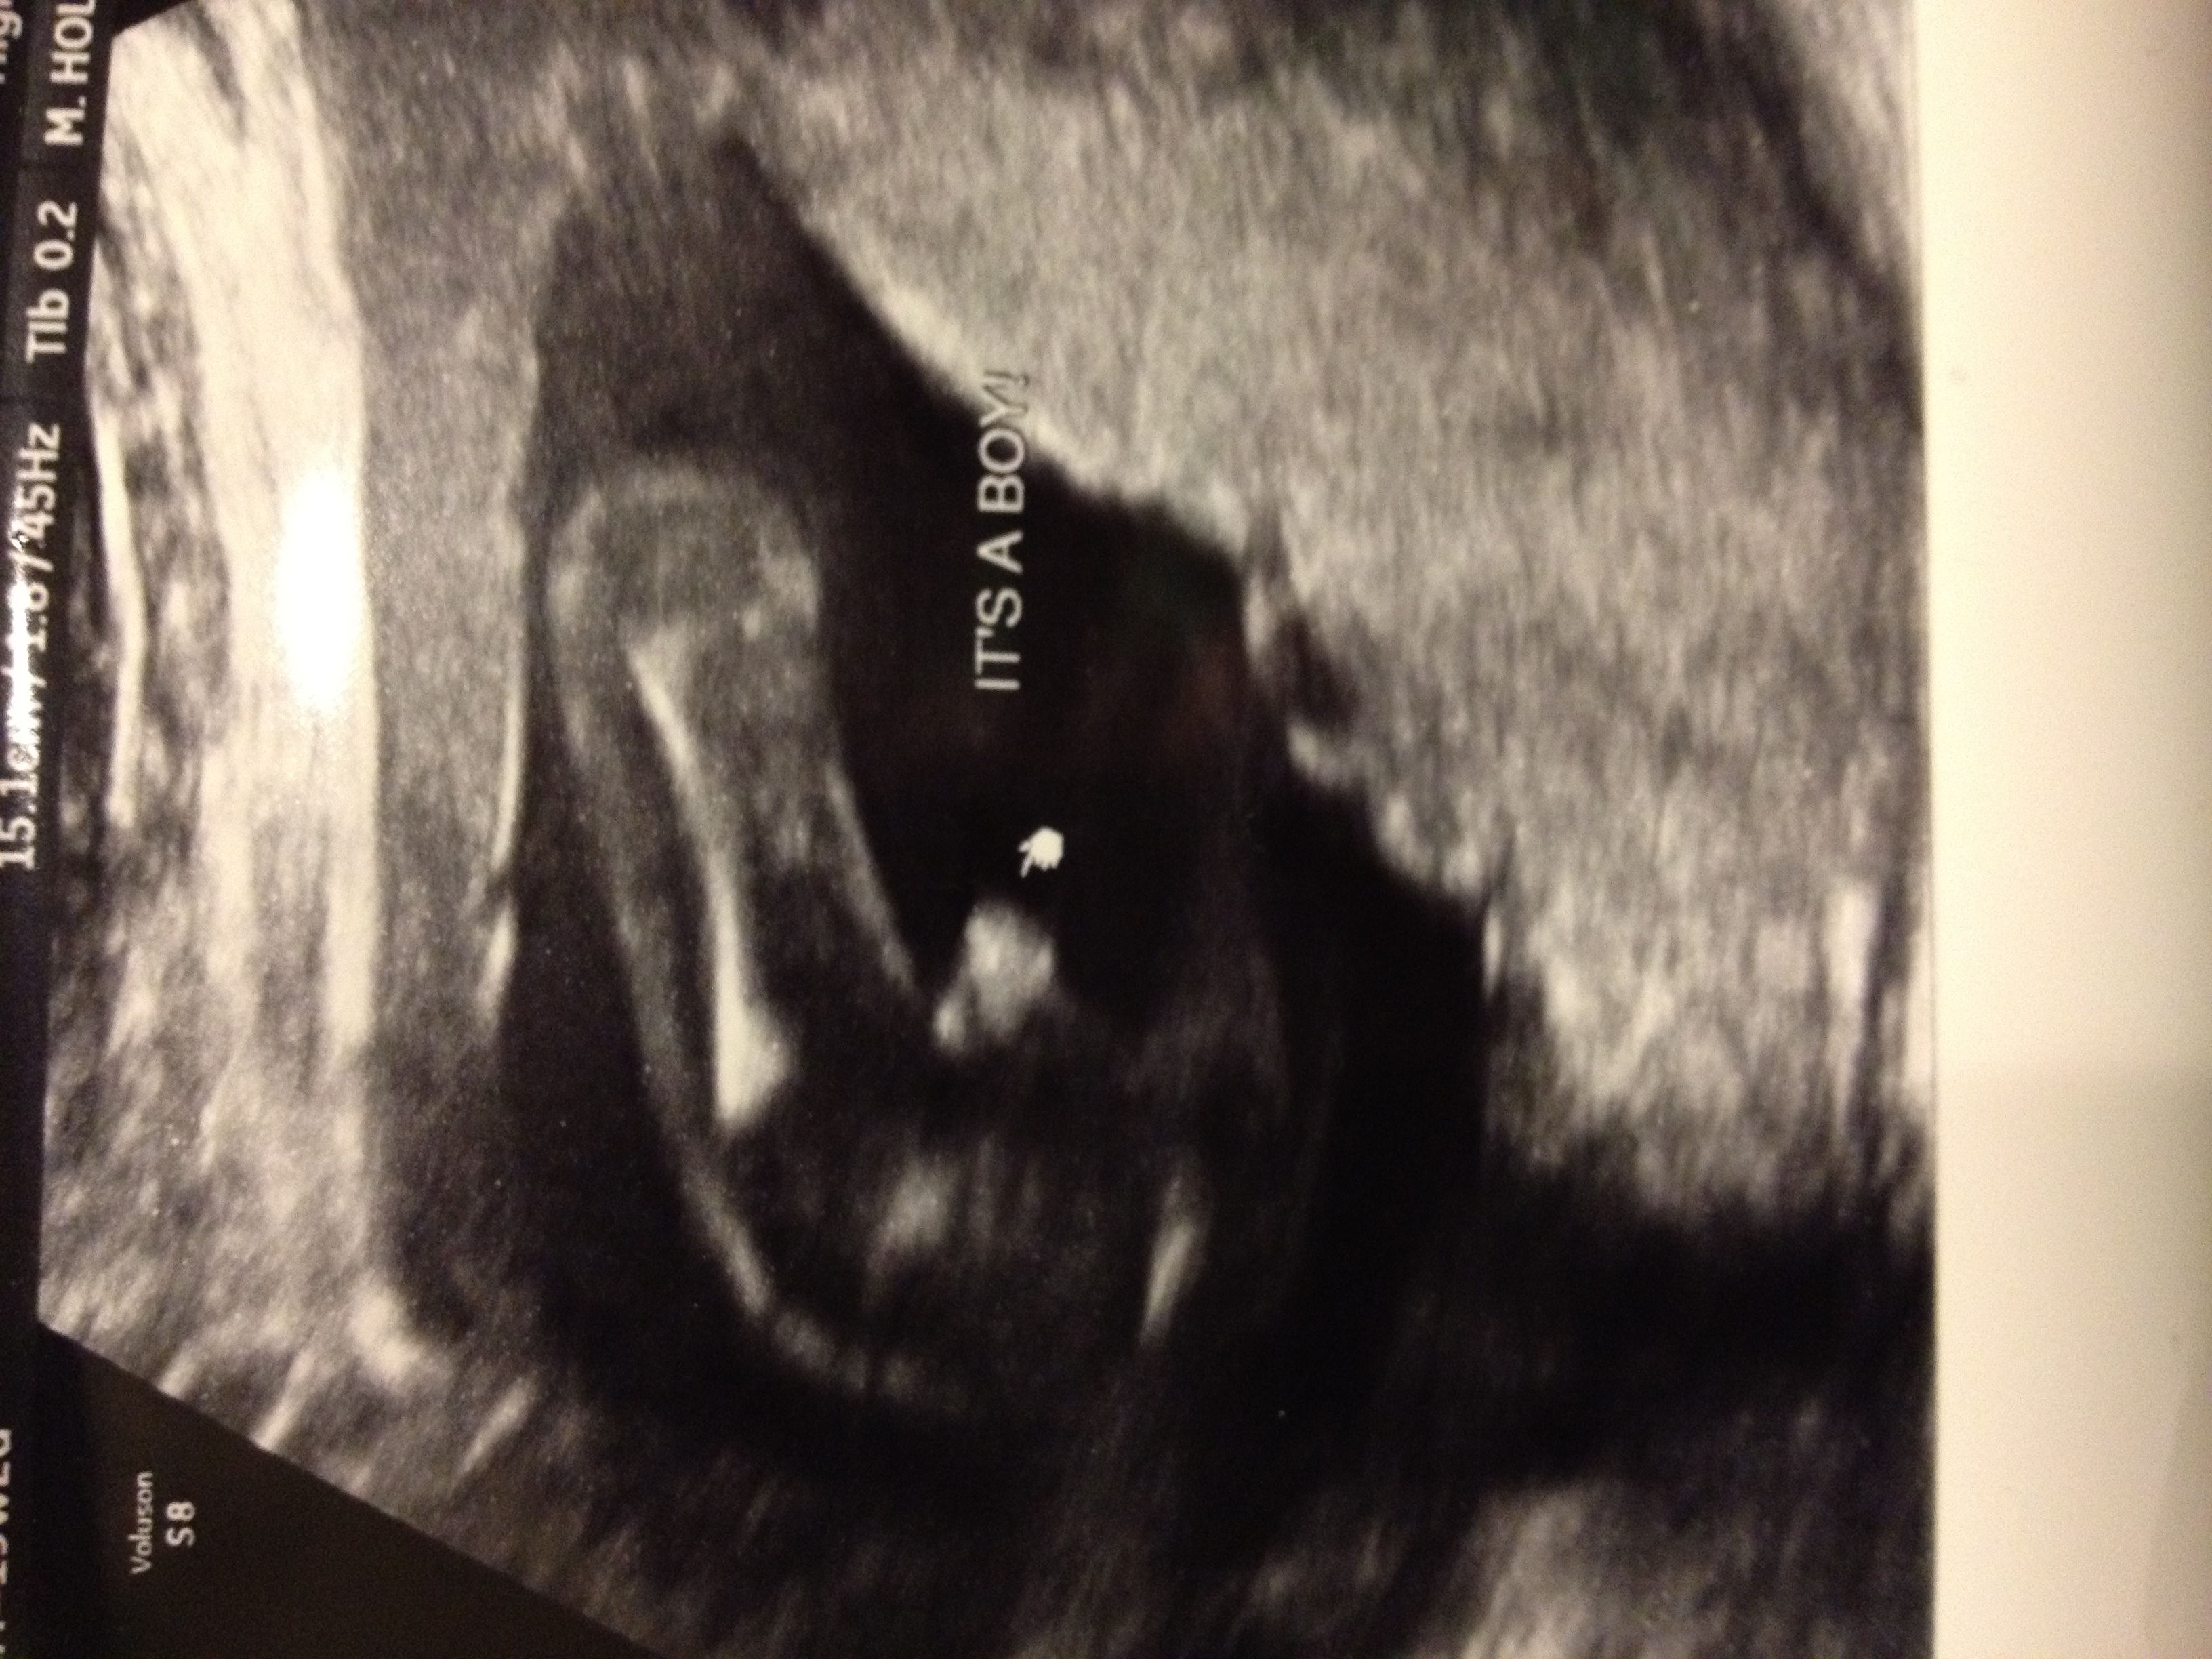

My little monkey!

DD is almost four, so next in line was a lil boy! But we would have been happier either way!

Can you post a pic of your ultrasound that you based the Ramzi theory off of please? Oh and was it an abdominal or vaginal ultrasound?